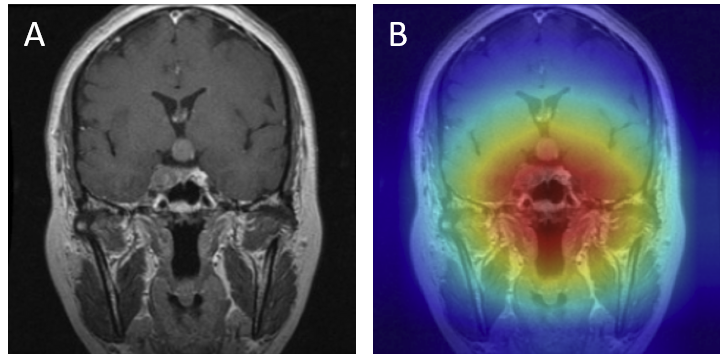

Grad-CAM visualizations of correctly classified cases confirm that the model focuses on regions consistent with radiological expectations. In these overlays, warmer colors (red and orange) highlight the areas where the network places the greatest emphasis during prediction, while cooler colors (blue) correspond to regions with minimal contribution. This distinction allows direct inspection of whether the model bases its decision on clinically relevant cues.

For gliomas, the heatmaps align with intra-axial lesions exhibiting infiltrative margins (Figure 8). Meningiomas are accurately identified at dural or peripheral attachment sites, consistent with their extra-axial presentation (Figure 9). Pituitary adenomas are localized to the sella turcica with concentrated red activation at the lesion boundaries (Figure 10). Finally, in no tumor cases, the activation maps remain diffuse or midline-focused without strong hotspots, consistent with normal anatomy (Figure 11). The correspondence between the model's attention and radiological landmarks indicates that the network is learning meaningful diagnostic features rather than relying on spurious correlations.

Figure 8: Glioma — original (A) vs. Grad-CAM (B), correct model prediction.

Glioma Correct

Figure 9: Meningioma — original (A) vs. Grad-CAM (B), correct model prediction.

Meningioma Correct